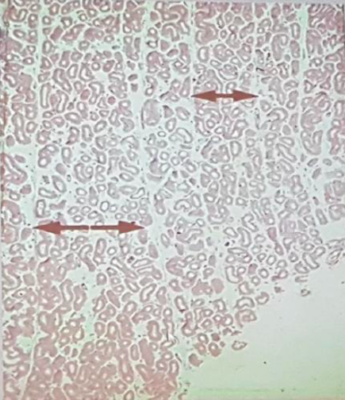

D'après les coupes que le prof présente dans son cours sur l'AGM il y a une chose que je ne saisi pas; les doubles flèches définissent un lobule ok, et chaque lobule possède en sa partie centrale un tube droit qui a pour rôle de drainer 5 à 6 TS. Donc chaque lobule ne contient que quelques TS, or les deux illustrations semblent autant l'une que l'autre montrer des lobules en possédant nombreux; est ce effectivement le cas et dans ce cas je veux bien une explication ou est ce que c'est simplement que l'on n'arrive pas bien à distinguer les cloisons des lobules sur ces coupes, ou encore est ce peut être d'autres structures que des TS ?